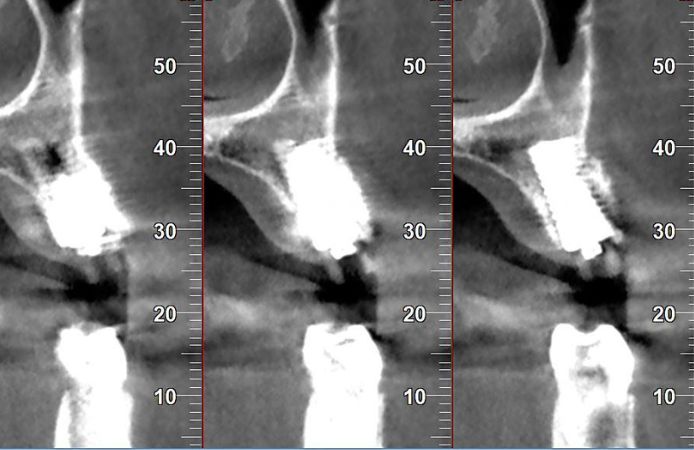

Figure 16.

The CBCT after 3.5 months healing (Figure 16) shows good integration of the Edge implant and bone regeneration in the initial defect. The ISQ had increased to 72/79 further indicating good integration.